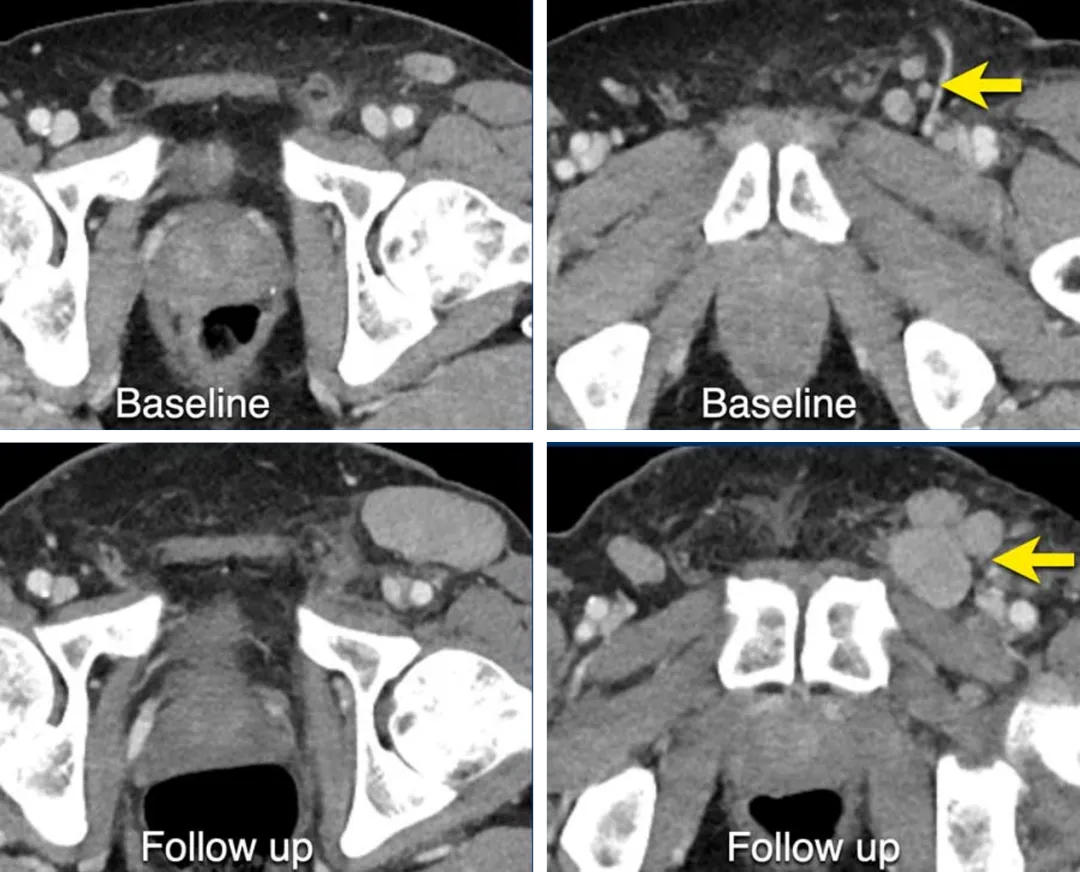

一名61岁男性黑色素瘤患者的CT图像,在基线时,腹股沟淋巴结较小,达不到靶病灶标准,被记录为非靶病灶,

后续随访显示淋巴结转移有明确的进展。